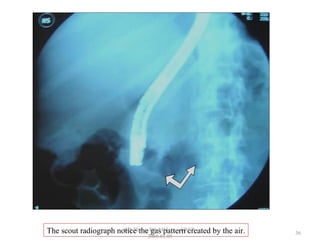

The scout radiograph notice the gas pattern created by the air. 36

The scout radiographnotice the gas pattern created by the air. 36 GB Thapa, BScMIT.........ERCP 2068.01.05

• Air is introduced into the gut to expand the

stomach & bowel for ease passage of the

endoscope.

• The endoscope is flushed by NS or CM since the

remaining air may give confusing shadows as of

biliary calculi. Scout film is taken.